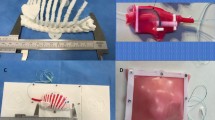

Two models, with identical diaphragmatic defects, were designed and built to simulate the operative steps of CDH repair via laparotomy and thoracoscopy with assessment of interobserver reliability of measuring the defect. Parental informed consent was obtained to use a pre-existing MRI scan from a foetus with a prenatal diagnosis of CDH for the purposes of designing a surgical simulation model. Stereolithography (STL) files were created from the patient MRI using the open-source software ITK-SNAP (v.3.8.0, www.itksnap.org). The size and relative proportions of the thorax, diaphragm and defect were delineated and segmented. The computer-assisted design (CAD) software Blender 3D (Blender Foundation, USA) and Fusion 360 (Autodesk Inc, USA) were used to clean, refine, and modify the ribcage, spine and pelvis.

For the thoracoscopic repair model, the left hemithorax was isolated and orientated in a right lateral position to simulate access to the left hemi-diaphragm. The ribs were reinforced at the vertebral bodies and costochondral joints with geometric shapes, and the scapula applied to the posterior ribcage. Geometric shapes were also added to the sternal side of the ribcage to allow fixation to the model base. For the model simulating repair via laparotomy, the entire rib cage was isolated and combined with the spine and pelvis as one component. This component was reinforced with geometric shapes to add strength and allow fixation to the base, simulating a baby lying supine.

The ribcage was 3D-printed (Prusa MK3) using a flexible thermoplastic polyurethane (TPU) filament (ERYONE, Shenzhen, China). TPU was selected to make the ribcage flexible but strong, allowing for repeated deformation without breaking, such as during rib retraction. The pelvis, spine, and model base, as well as 3mm laparoscopic instrument ports, were printed using a rigid polylactic acid (PLA) filament (ERYONE, Shenzhen, China).

Using measurements derived from the foetal MRI, moulds for silicone casting of soft organs and tissues were 3D-printed, including diaphragm, lung, liver, spleen and bowel. Platinum-catalysed silicone (Smooth-On Inc., Pennsylvania, United States) of varying hardness, and dyed with pigment, was used to maximise realism. The silicone components were applied to the 3D-printed model (Fig. 1). The silicone diaphragm was constructed based on measurements from the patient MRI. These measurements were replicated in the CAD software to create a diaphragm measuring 42 mm by 75 mm (Fig. 2), therefore, each hemi-diaphragm measured 42 mm by 37.5 mm. The entire diaphragm was used in the model of repair via laparotomy and the left hemi-diaphragm was used in the thoracoscopic repair. The defect was measured on the MRI and was added to the silicone diaphragm after curing. This measured 15 mm by 15 mm.

These two models assess several steps in the CDH repair procedure. The model provides anatomical landmarks for planning access. The models simulate: incision or thoracoscopic port placement, navigation of the chest cavity with a camera, identification of the defect, reduction of its content, assessment of the defect size, direct primary closure or patch placement and wound closure. Additionally, the models can be reused with replacement of parts that are sutured or incised.